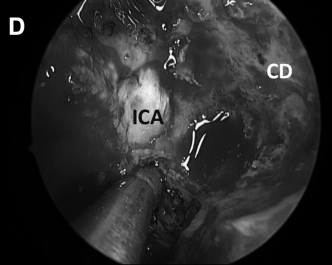

▼从该切口可暴露右颈静脉结节区域的充足手术通道(图8E和F)。

▼然后肿瘤被切除。在图8G中,可见肿瘤基底部暴露,并且颈静脉孔神经部组织可以通过组织质地来区分。

CD,斜坡凹陷;S,蝶鞍;SR,蝶嘴;T,肿瘤。